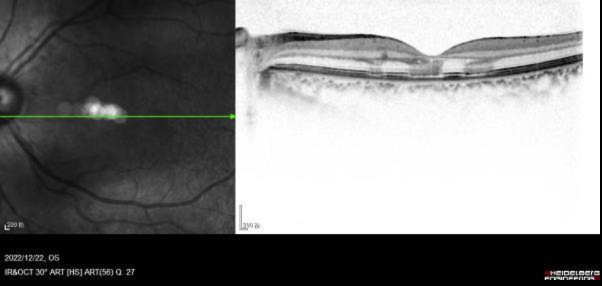

经眼部专科检查,她的双眼黄斑区可见暗红褐色病灶,色素紊乱,外层视网膜高反射病灶,集中在黄斑区视网膜外核层,椭圆体带和嵌合体带断裂。结合病史及专科检查,医生确诊其为急性黄斑区神经视网膜病变。